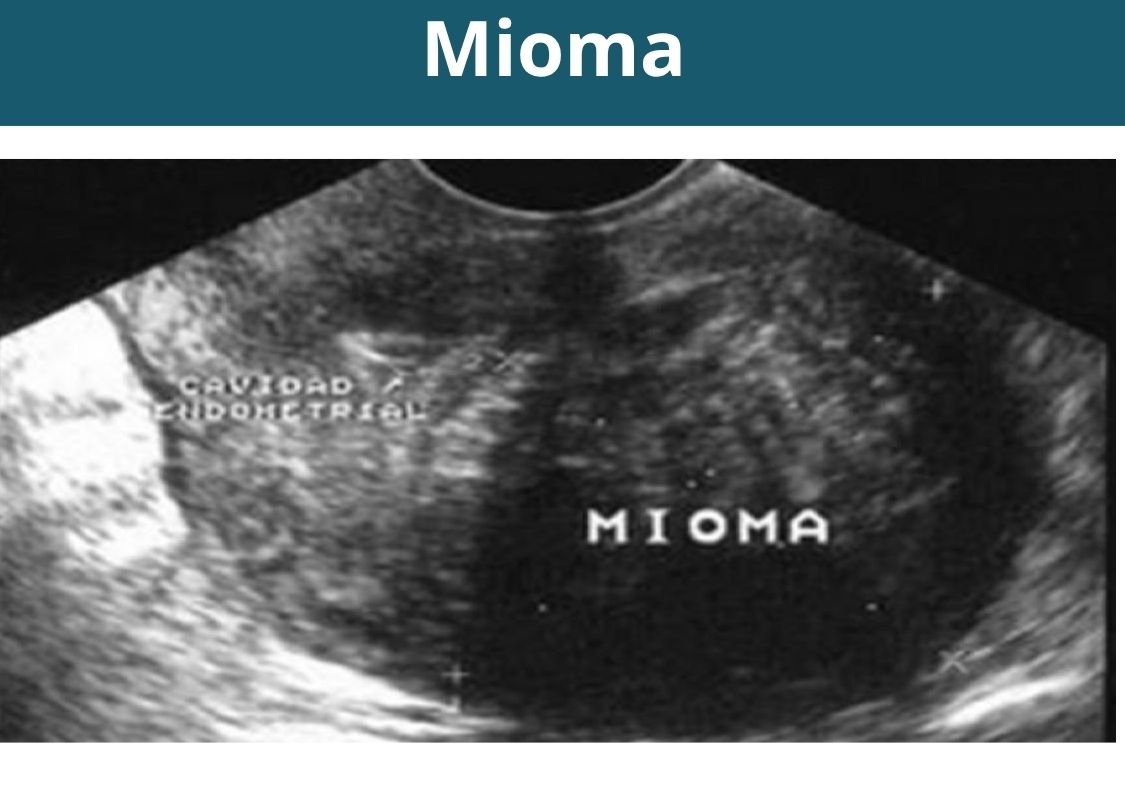

- Ultrasonografía pélvica abdominal (útero y ovarios).

- Ultrasonografía transvaginal (útero y ovarios).

Otras ultrasonografías